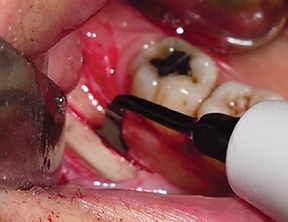

The recipient site was then prepared by perforating the cortical plate with a piezoelectric insert (ES012T) to expose the marrow spaces and promote vascular ingrowth (Fig. 14).

Fig. 14: Recipient site prepared by perforating the cortical plate

Block by Block